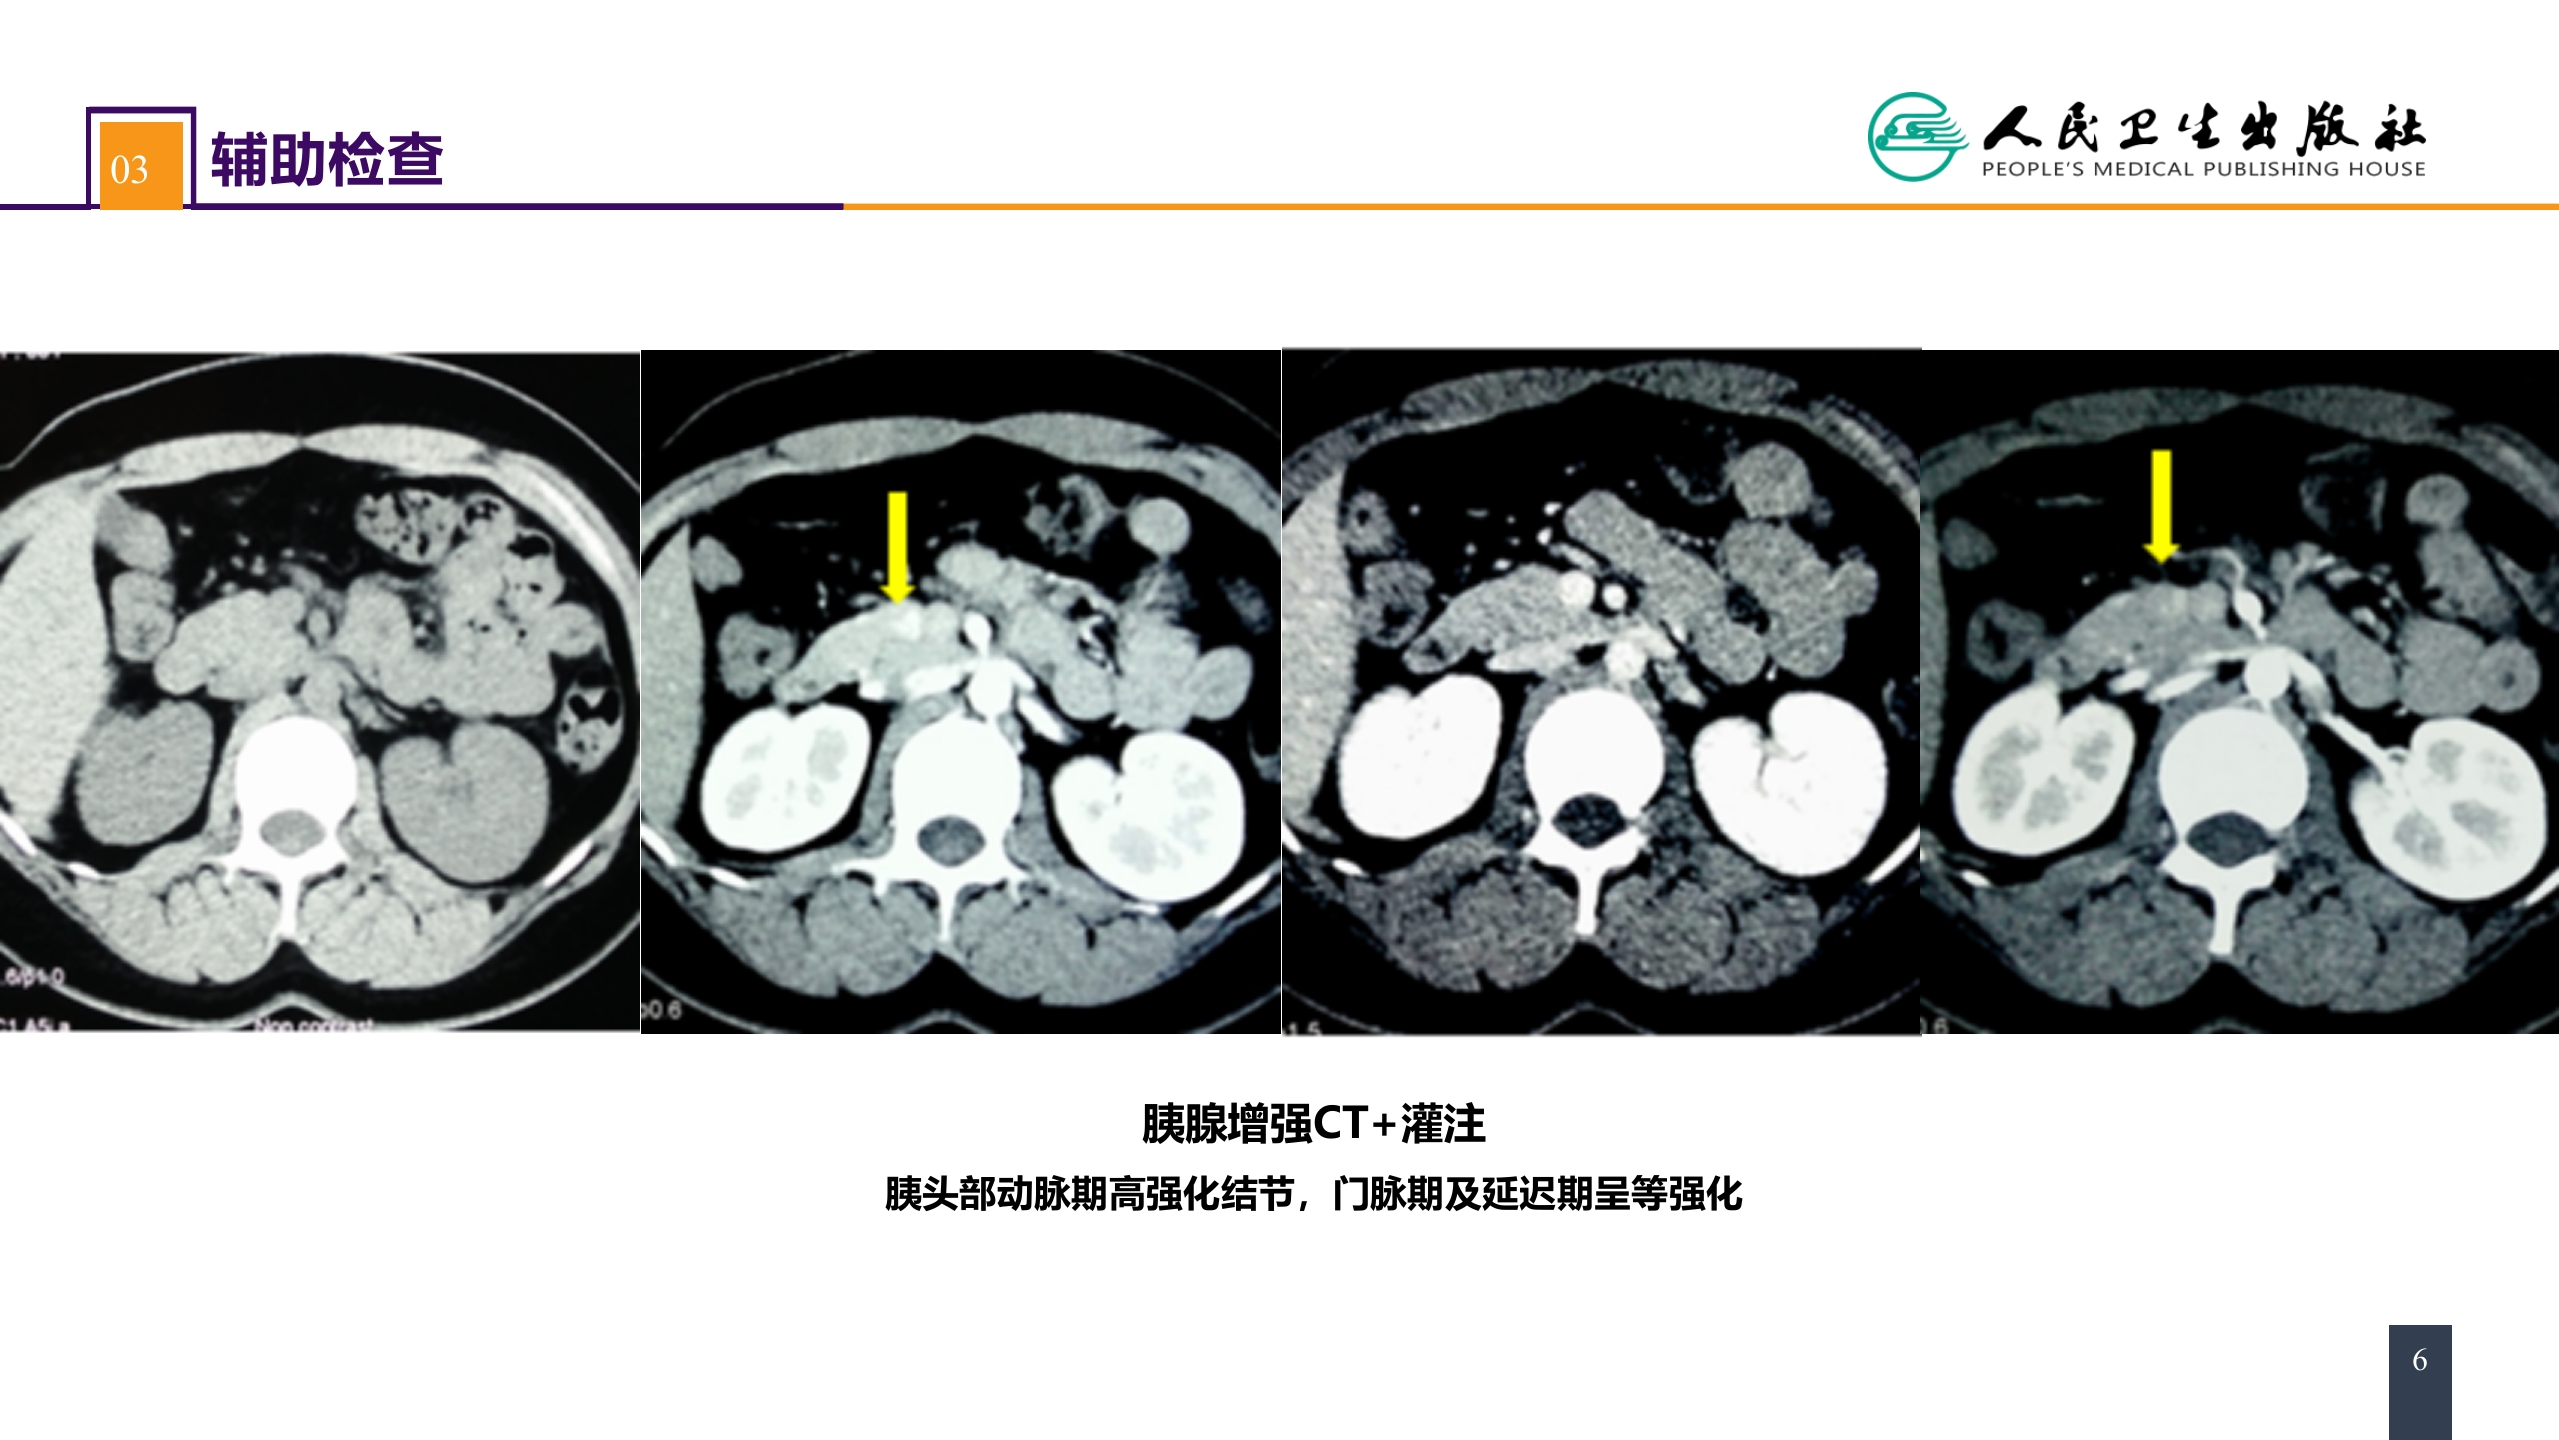

第四十一章 胰腺疾病 案例分析-胰岛素瘤